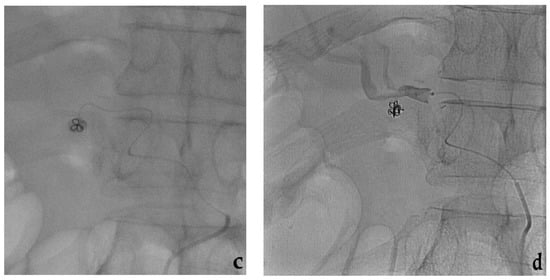

3.6. Embolization with Plugs, Microplugs

- Lopera, J.E. The Amplatzer vascular plug: Review of evolution and current applications. Semin. Interv. Radiol. 2015, 32, 356–369. [Google Scholar] [CrossRef]

- Wang, W.; Li, H.; Tam, M.D.; Zhou, D.; Wang, D.X.; Spain, J. The amplatzer vascular plug: A review of the device and its clinical applications. Cardiovasc. Interv. Radiol. 2012, 35, 725–740. [Google Scholar] [CrossRef]